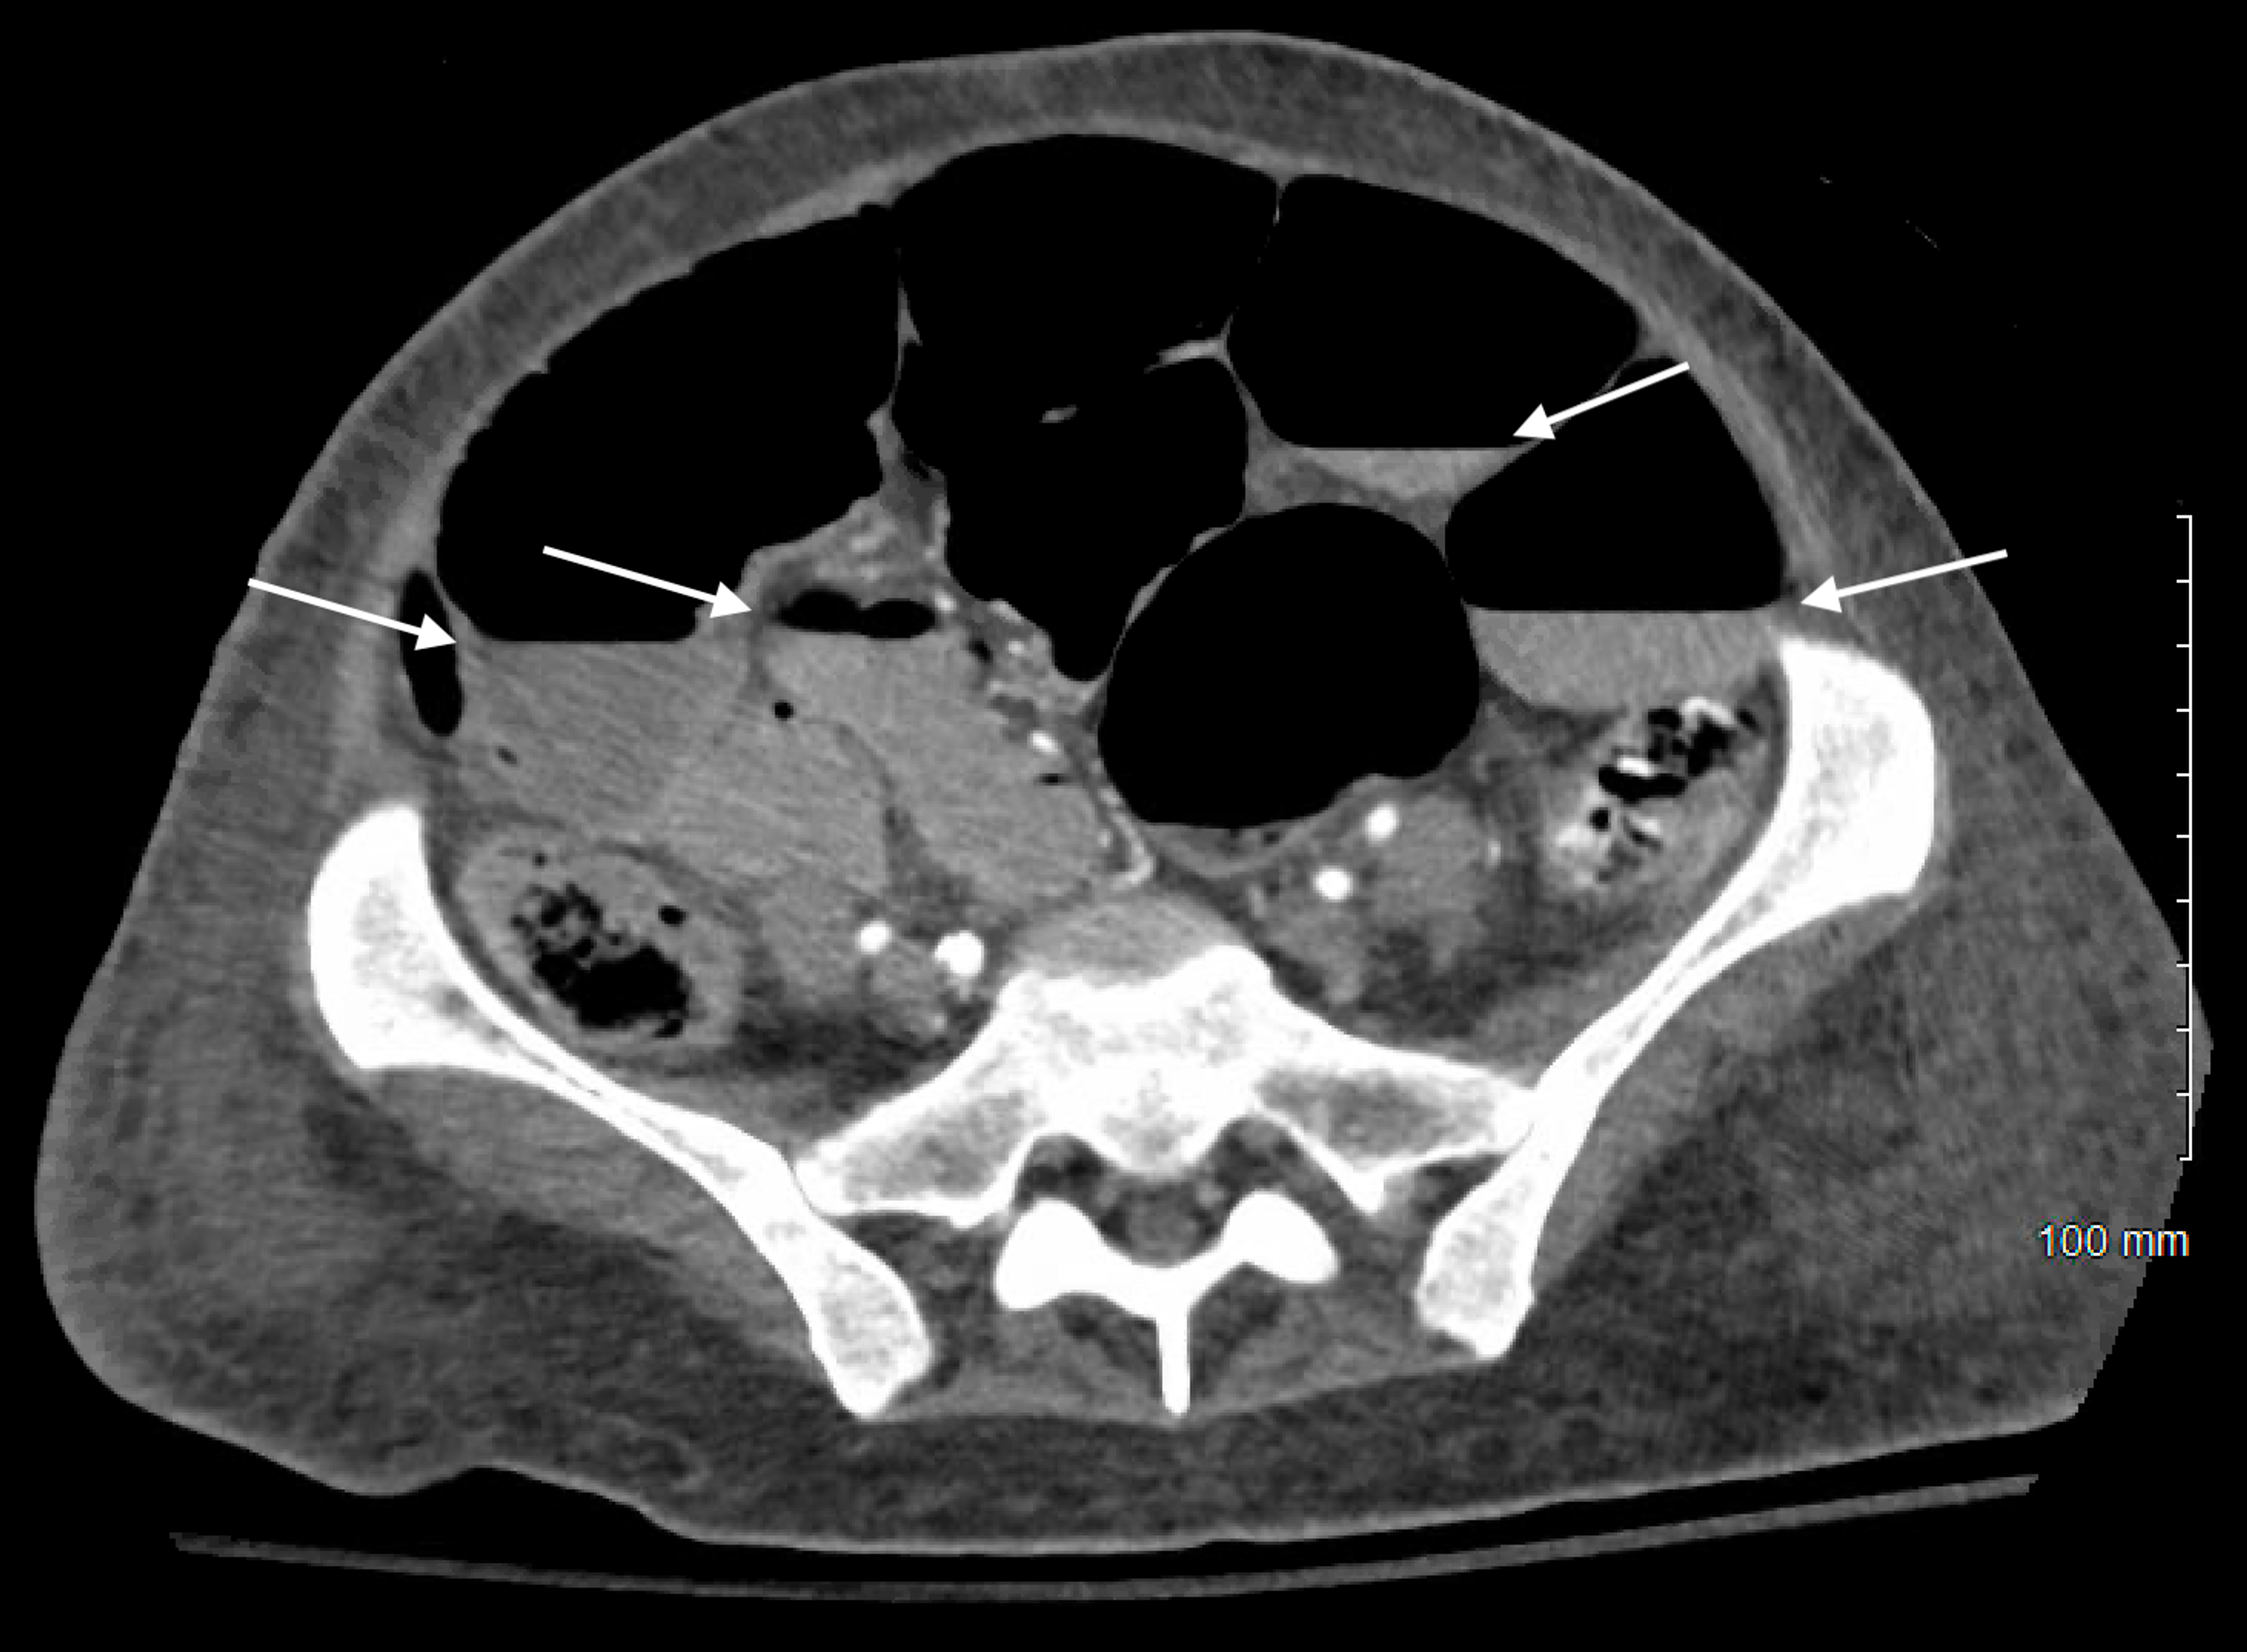

Review of SmallBowel Obstruction The Diagnosis and When to Worry What Causes Air Fluid Levels In Bowel Obstruction • since this is not a mechanical obstruction, there should be gas seen in the rectum or sigmoid. the pathologic effects of acute intestinal obstruction are fluid and electrolyte imbalances, and mechanical consequences of increased luminal pressure. an edematous bowel wall that measures more than 3 mm is. What Causes Air Fluid Levels In Bowel Obstruction.